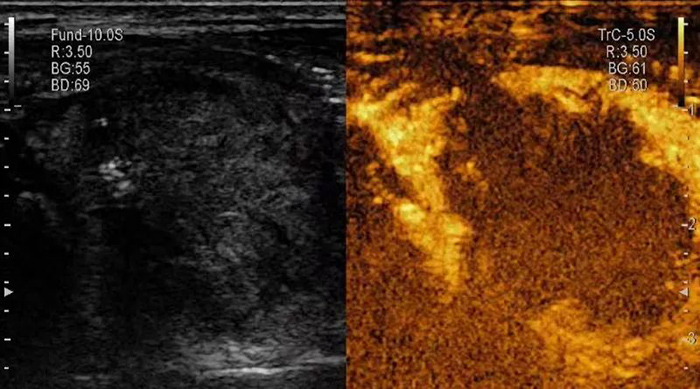

此方法是通过高温灭活的方式使肿瘤细胞产生凝固型坏死,能完全阻断肿块内部微血管循环,使肿瘤完全坏死,一般经过半年到1年的时间大部分坏死肿瘤均可吸收,复发率低。

▲消融后,超声造影提示结节内完全无增强,呈“黑洞征”,表明肿瘤被完全杀死。